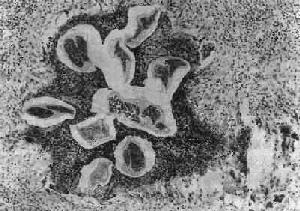

馬來血絲蟲病馬來血絲蟲病

班氏絲蟲病呈世界性分布,主要流行於熱帶和亞熱帶;馬來絲蟲病僅限於亞洲,主要流行於東南亞。中國許多省份均有班氏絲蟲病及馬來絲蟲病感染的現象,然以東南沿海各地:上海、浙江、福建、廣東、廣西等地感染率較高,其中也以上述各省兩種絲蟲混合感染的比例為最高,平均約在20%上下。另據范秉真及許雨階的研究,班氏絲蟲應為台灣地區的源發性病症,且本島應該沒有馬來絲蟲症的病例。但1949年到50年代初期,由於國府自大陸撤軍來台,以因而帶入部分感染馬來絲蟲症的既有病例個案。根據兩人的追蹤調查,大陸來台受檢人士之血絲蟲患者約有27,000人,其中二分之一感染馬來絲蟲;而1955年由浙江大陳島撤退來台之島民竟有96%的馬來絲蟲感染率。比較値得注意的是,靠近大陸地區的馬祖、金門兩島,除了由大陸撤退人士帶來的馬來絲蟲個案外,儘管兩地血絲蟲症感染率都高達45%上下,兩地之本土個案(localcases)完全都屬於班氏血絲蟲症的患者。除了國府控制下之台灣、澎湖、金門、馬祖等地完全沒有馬來絲蟲的感染個案外,大陸來台人士之馬來絲蟲感染者經居住數十年後,仍未發現有本土馬來絲蟲症之個案,除得以認為國府血絲蟲症防治計畫確實有所成效外,似乎也顯示這四處地方並不具有得以有效傳播馬來絲蟲的媒介。